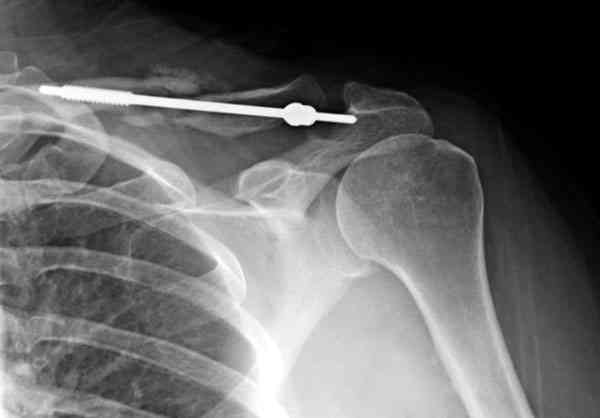

ГГШ> Результат стационарного лечения приведен на рентгенограмме (Xray_3).

Это картинка то есть через неделю после травмы, при выписке? Более чем приемлемо.

после изучения рентгенограмм могу сказать следующее:

1) после репозиции стало хуже

2) стояние фрагментов при выписке идентично таковому при пступлении - с выраженным смещением

Ув. Г.В.! На мой взгляд, никакого ухудшения стояния отломков на втором снимке нет!!! Просто проекция среднего снимка несколько под другим углом, и увеличение межотломкового расстояния не что иное , как проекционное искажение. По - поводу колец... Конечно они иммобилизуют плечо лучше , чем Cuff and Collar, хотя не намного, но что если разовьётся парез брахиального сплетения???

Уважаемая Г.В. Полностью согласен с Вашим постом.Закрытая репозиция и кольца Дельбе отлично зарекомендовали себя за 35 лет практики. В обсуждаемом случае представленные Р-граммы сами говорят за себя, 1 снимок (до лечения) и 3 снимок (после лечения) абсолютно идентичны, 2 снимок сделан в несколько иной позиции.Как говорится "комментарии излишни". Согласитесь, что результат лечения мог бы быть и лучшим.